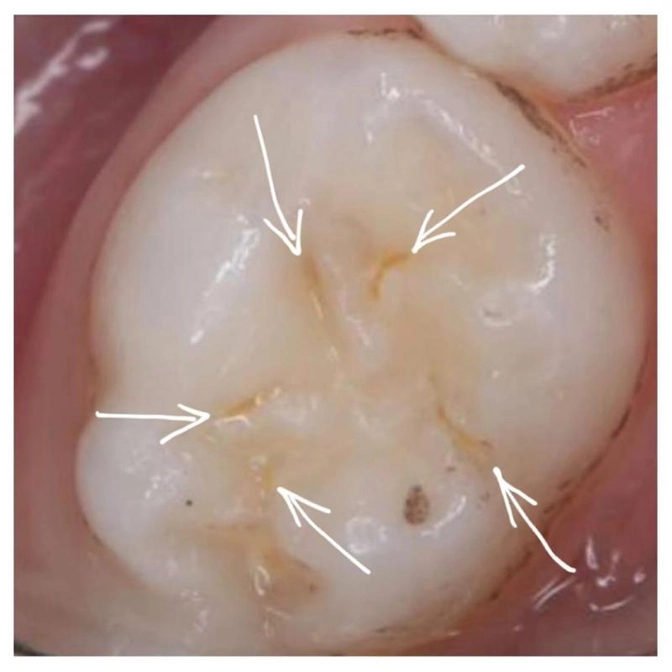

На очередном визите я провела визуальный и инструментальный осмотр зуба и обнаружила кариес на самом раннем этапе.

Как всегда он подкрался незаметно и спрятался в фиссуре пятого зуба.

Это очень часто встречающаяся проблема и ее не видно глазу!

Кариес появляется в виде еле заметных желтоватых полосочек.

Его можно увидеть при определенном освещении, или когда мы высушим зуб в условиях стоматологического кабинета.

Эту фотографию я сделала, чтобы максимально увеличить и показать родителям.